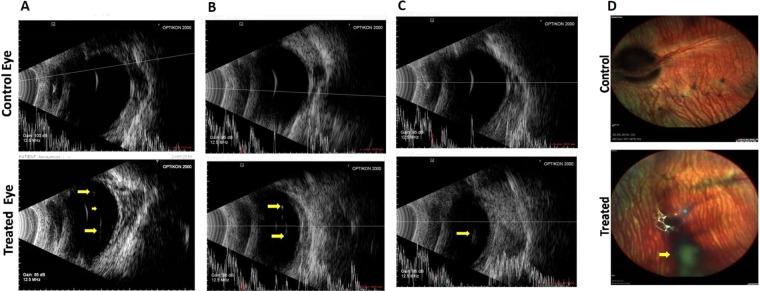

Clinical evaluation (Indirect ophthalmoscope and B-ultrasonography)

Post injection, after 24 h, vitreous was still clear in most of the treated eyes, except rabbits 1 and 2 which showed a mild vitreous haze; however, in these eyes too, the vitreous cleared up by day 8. There were no unwanted abnormalities like vitreous or retinal haemorrhage, retinal edema, retinal detachment, or any effect on the lens in any of the control or treated animals (Supplementary Table 1). It was found that in only one animal (rabbit number 3), vitreous had media grade 2 on day 4 and remained like this till day 8. The presence of fibrin in the anterior chamber in some animals resolved with time (i.e., by day 8). Treatment with the reagents led to a floating posterior hyaloid membrane as seen by indirect ophthalmoscope in eyes with complete PVD, whereas, in control eyes, there was no such detachment. B-scan ultrasonography demonstrated a complete (Fig. 8A,B) or partial (Fig. 8C) detachment of the posterior hyaloid upon intravitreal injection of reagents, whereas in control eyes (PBS), there was no evidence of vitreous detachment. On 8th day, multicolor fundus pictures revealed no signs of retinal toxicity, vitreous opacity, retinal detachment, or haemorrhage, and in eyes with complete PVD, the posterior hyaloid membrane formed a shadow due to PVD, seen in the image as a dark spot (Fig. 8D).

Scanning electron microscopy

Scanning electron microscopy showed dense vitreal collagen fibrils on the inner surface of retina or ILM, with intact vitreoretinal adhesion on the retinal surface in the control eye injected with PBS (Fig. 9). In eyes treated with reagents, there were no collagen fibrils on the retina. In some cases, few remnants of collagen fibrils of the cortical vitreous were seen; the SEM observations were in line with the B-ultrasonography and indirect ophthalmoscopic findings.

The status of animals on 8th day was as follows: The B scan ultrasonography data suggested occurrence of complete PVD in 5/10 eyes, partial PVD in 3/10 eyes and no PVD in 2/10 eyes treated with reagents (Table 1). Indirect ophthalmoscopy hinted at occurrence of complete PVD in 3/10 eyes, partial PVD in 4/10 eyes and no PVD in 3/10 eyes. SEM data suggests incidence of complete/partial PVD in 8/10 eyes. However, SEM has the disadvantage of examining sections of one half of the eye (while the other half was used for H&E staining), and moreover, only parts of the first half are being observed at a given time, unlike B scan ultrasonography or indirect ophthalmoscopy, which view the entire eye on live animals (Table 1). Overall, intravitreal injection of CBD and RCBD resulted in PVD in 7 out of ten animals, considering all three methods of evaluation.